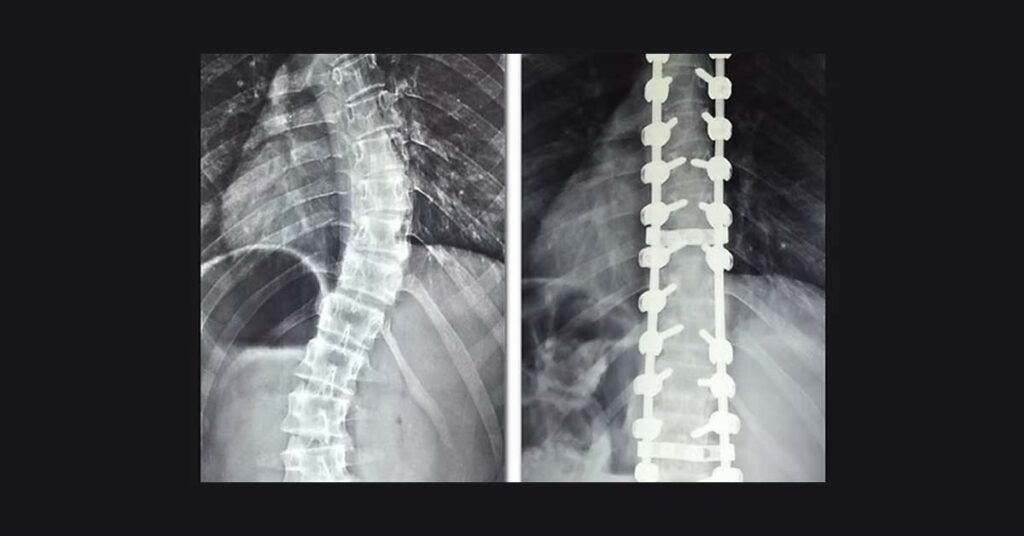

A técnica cirúrgica, que frequentemente utiliza a fusão espinhal com hastes metálicas, muitas vezes pode reduzir consideravelmente o grau de curvatura.

Isso resulta em uma postura mais alinhada.

A fusão espinhal reduz a flexibilidade na área operada, o que pode limitar alguns movimentos.